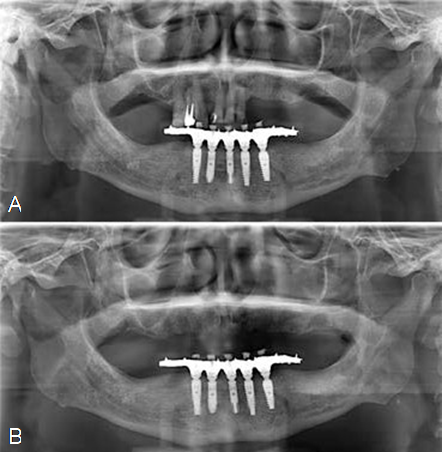

Radiographically, the patient had a partially edentulous upper arch, generalized bone loss, low quality bone (type III) and pneumatization of the right maxillary sinus (Figure 2.A).

The remaining teeth were extracted 6 months prior to implant rehabilitation procedures in the upper arch (Figure 2.B).